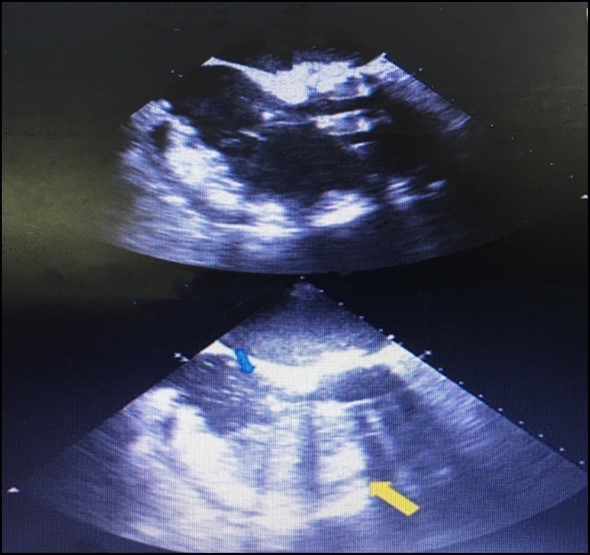

We describe a case in which an easy action, such as instillation of agitated saline, allowed us to confirm a major complication related to pericardiocentesis. A 62-year-old man with a history of mitral and aortic valve replacement 2 weeks earlier presented with complaints of dyspnea and asthenia. Laboratory tests and chest x-ray revealed the presence of massive right hemothorax and severe secondary anaemia. Despite blood transfusion and chest tube insertion, the patient’s hemodynamic situation continually worsened, and he finally developed cardiac arrest. During cardiopulmonary resuscitation, an urgent echocardiogram showed severe pericardial effusion. Therefore, pericardiocentesis by a subxiphoid approach was performed. After stabilisation, the patient was transferred immediately to coronary care unit. The pericardial tube had been left in place. Continuous blood drainage was noticed after shifting and agitated saline was injected through the drainage tube to define its precise location. Right ventricular opacification was observed during a repeat echocardiogram with massive bubbles confirming the drainage tube was placed actually within the right ventricle (Figure 1). This case emphasizes the importance of instillation of agitated saline as a supplementary technique while performing echo-guided pericardiocentesis in order to reduce the likelihood of cardiac chamber perforations. Subsequent sections will discuss more frequent complications of pericardiocentesis including rates, severity, and other important procedural and non-procedural considerations.

Figure 1.The complete opacification of the right ventricle (yellow arrow) and the presence of some bubbles within the right atrium (red arrow),denoting that the tip of the drainage tube is malpositioned within the right ventricle.

When the procedure is performed, the pleura and lung are not injured because of the presence of the cardiac notch in this area 16. The phrenic nerve, with its accompanying vessels, descends between the fibrous pericardium and mediastinal pleura on each side. Inferiorly, the pericardium is separated by the diaphragm from the liver and fundus of the stomach 14 (Figure 1).Ribs and their counting is done from the second costal cartilage is identified first at the level of sterna angle; thereafter the ribs are palpated and counted downwards and laterally away from the sternum in order to avoid confusion due to crowding of the cartilages of fifth, sixth and seventh ribs as they approach the sternum. The sterna end of the first rib can be felt immediately below the sternal end of the clavicle.